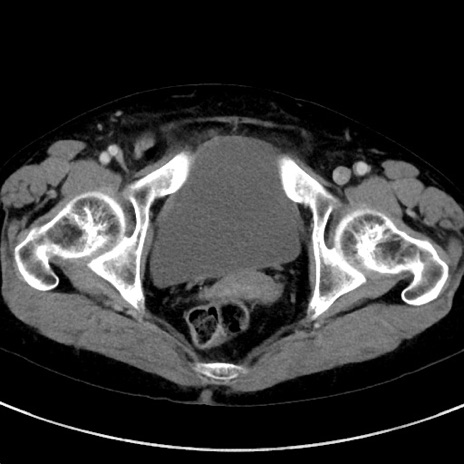

症例23(横断像)

【症例】70歳代女性

【主訴】下腹部痛・嘔吐

【現病歴】2日前より腹痛あり。昨日嘔吐あり。症状改善しないため来院。

【既往歴】胃GISTに対して胃部分切除後。

【身体所見】BT 37.1℃、BP 128/77mmHg、腹部:平坦・軟、下腹部に圧痛あり。

【データ】WBC 10200、CRP 0.31